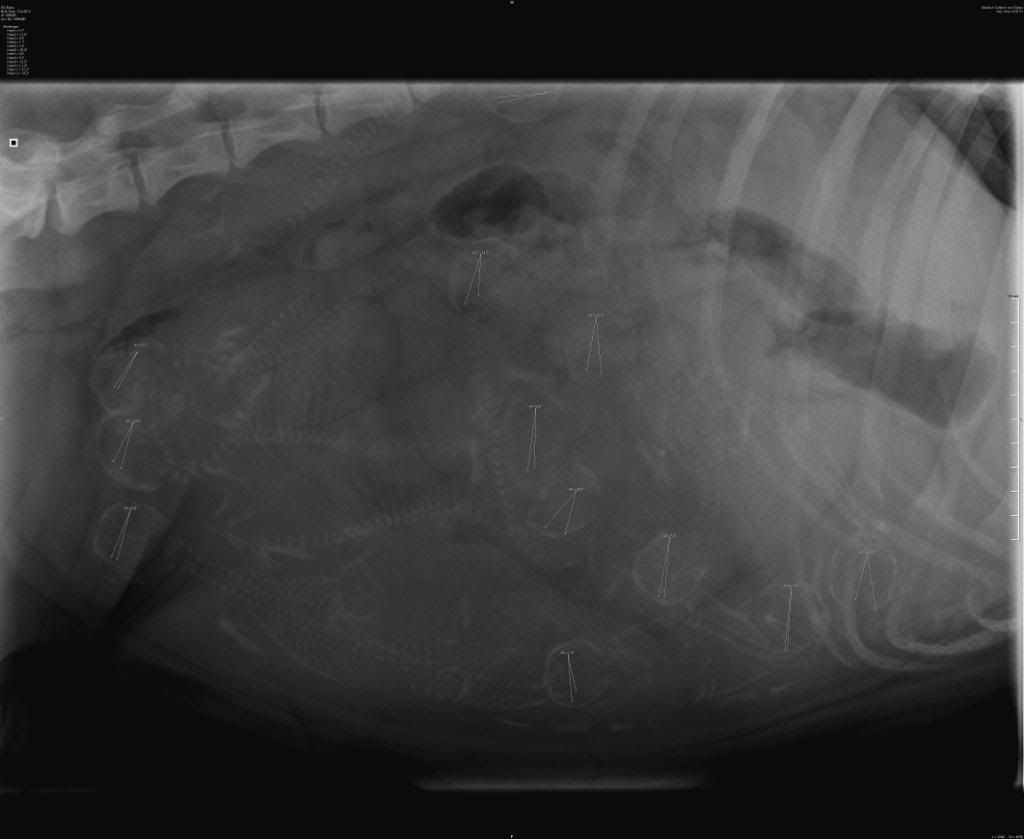

Maar ik zit toch echt een beetje met een dik vraagteken boven m'n hoofd. Ik kwam deze post tegen:

Maar ik zit toch echt een beetje met een dik vraagteken boven m'n hoofd. Ik kwam deze post tegen:

Uiteindelijk zijn er "maar" 10 via keizersnede geboren??elly17 schreef:balou zit vandaag op 55 dagen dus de bevalling zit er aan te komen gister rx laten maken dokter zegt 10 ik denk zelf 12 mijn vraag aan jullie hoeveel zien jullie er .

Ik zie op deze foto maar 10 schedels. Twee "merkjes" staan in iets anders. De middelste staat in een ribbenkastje en die daar iets schuin rechtboven in iets ondefinieerbaars . Blijven er 10 over. Dus dat klopt wel.Rosan's Sandra schreef:Uiteindelijk zijn er "maar" 10 via keizersnede geboren??elly17 schreef:balou zit vandaag op 55 dagen dus de bevalling zit er aan te komen gister rx laten maken dokter zegt 10 ik denk zelf 12 mijn vraag aan jullie hoeveel zien jullie er .